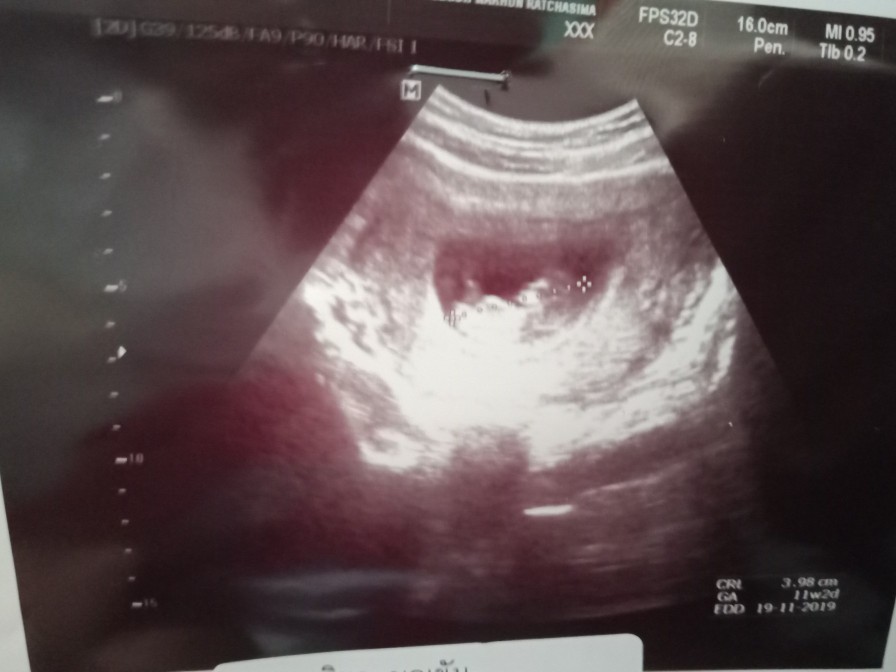

บ้านนี้ตอน12w2dค่ะ